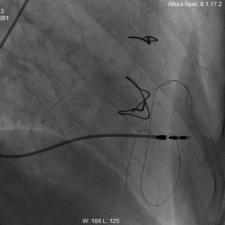

9. 瓣膜通过二尖瓣瓣环,准确2:8定位后扩张释放